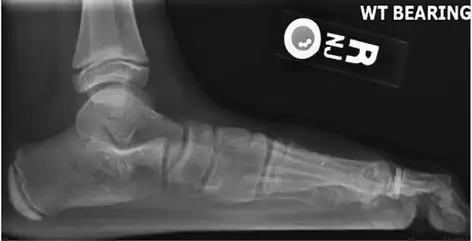

- Lateral X-ray of a flat foot with C-sign, which is a bony bridge between the talar dome and sustentaculum tali, in combination with a prominent inferior border of the sustentaculum tali. This represents a talocalcaneal coalition, which is an abnormal connection between the talus and calcaneus and is thought to cause the flat foot deformity in this case.[6]

On plain radiography, flat feet can be diagnosed and graded by several measures, the most important in adults being the talonavicular coverage angle, the calcaneal pitch, and the talar-1st metatarsal angle (Meary's angle).[11] The talonavicular coverage angle is abnormally laterally rotated in flat feet.[11] It is normally up to 7 degrees laterally rotated, so a greater rotation indicates flat feet.[11] Radiographies generally need to be taken on weightbearing feet in order to detect misalignment.[12]

- Weight-bearing lateral X-ray showing the measurement of calcaneal pitch, which is an angle of the calcaneus and the inferior aspect of the foot, with different sources giving different reference points.[13] A calcaneal pitch of less than 17° or 18° indicates flat feet.[11]

- Same lateral X-ray showing the measurement of Meary's angle, which is the angle between the long axis of the talus and first metatarsal bone.[11] An angle greater than 4° convex downward is considered a flat foot, 15° - 30° moderate flat foot, and greater than 30° severe flat foot.[11]